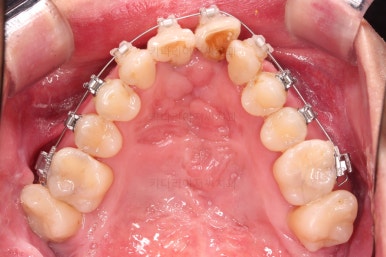

교정 10개월째인데, 악궁형태 많이 좋아졌고, 가지런한 느낌도 많이 좋아졌습니다.

최종적으로 교합과 현실성 있는 목표를 다시 점검하고요.

예후가 불투명했던 대문니 2개를 살려 쓸 수 있는지, 교정 종료 전에 빼고 보철로 해결해야 하는지 최종평가를 하게 됩니다.

뼈가 좋지 못하고, 장기적으로 사용하기에는 한계가 있어 보이지만 유지철사로 단단히 엮어놓고 본인도 조심히 사용하신다면 당장은 발치하지 말고 최대한 오래 써보자고 결론을 냈습니다.